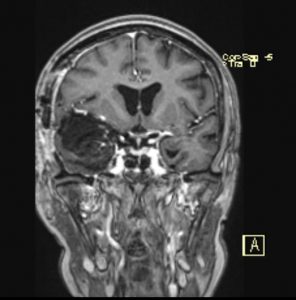

Ασθενής 69ετών με συμπτώματα βραδυψυχισμού και έκπτωση γνωσιακών λειτουργιών.

Ο απεικονιστικός έλεγχος με μαγνητική τομογραφία ανέδειξε ευμεγέθη εξεργασία δεξιά, συμβατή με μηνιγγίωμα πτέρυγας σφηνοειδούς οστού.

Πρόκειται για ένα μεγάλο μηνιγγίωμα το οποίο εμπλέκει πολύ σημαντικά ανατομικά στοιχεία όπως την καρωτίδα και τους κλάδους της και το δεξί οπτικό νεύρο.